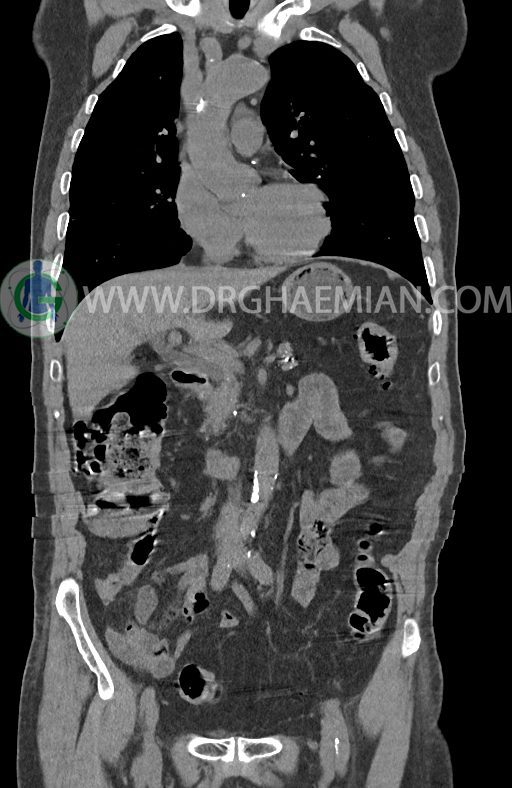

در سی تی اسکن اسپیرال ریه ها و مدیاستن، شکم و لگن با و بدون کنتراست وریدی (مولتی دیدکتور 16 با مقاطع ظریف و بازسازی کرونال) :

–افزایش ضخامت تومورال دیستال مری و GEJ در سگمانی به طول 4cm-5cm (T2 or T3)

-3 لنف نود رژیونال با SAD ≤ 9 mm دیده می شود. (N2)

–توده هیپودنس به قطر 10mm در پارانشیم طحال مشهود است. Quadriphasic MRI پیشنهاد می گردد.

–آتروفی نسبی پانکراس همراه با فوکوس های کلسیفیه ی منتشر پارانشیم مطرح کننده ی پانکراتیت مزمن

-CBD بسیار دیلاته (16mm) همراه با دیلاتاسیون مجاری داخل کبدی سنترال بدون شواهد سنگ یا توده در مسیر

–کیست های کورتیکال متعدد هر دو کلیه به بزرگترین قطر 56mm

–پروستات به دیامتر عرضی بزرگ حاوی فوکوس کلسیفیه

نتیجه : T(2or3)/N2/M0